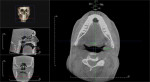

After SBT fitting, the patient then had two cone-beam scans performed—one in the pre-fitting habitual position and the other while in the final position determined by the SBT using the locked AMPG. The CT scans were performed using a 360-degree CBCT portable scanner (Kodak Model 9500 Cone Beam CT, Carestream Dental, www.carestream.com) while in a seated position. (Authors’ note: In all cases, lowest possible dosage was used by the CBCT technician. The maximum dose of the Kodak 9500 CBCT for the study procedure was 93 microsieverts.)

The first scan was taken with the patient relaxed, breathing through the nose, with the tongue placed behind the front incisors. The second scan was taken with the AMPG—still locked in its final position—placed back in the patient’s mouth, with the patient breathing through the nose and with the tongue placed behind the front incisors. The patients’ CBCT scans were measured using Invivo5 software (Anatomage Dental, https://dental.anatomage.com). The measurements were taken at the same slices for the pre- and post-treatment scans. To provide a sense of procedural time, from start to finish, each cone-beam procedure required about 20 to 25 minutes from setup to completion. The titration of each patient’s mandible took less than 20 minutes. Outcome measures included pre- and post-fitting airway data, temporomandibular joint (TMJ) position, and tongue position. The airway measurements were taken from the CBCT scans at the narrowest portion of the oropharynx. A-P measurements were defined from the patient’s habitual bite position.

Table 2 summarizes the results of each patient’s adjusted mandibular position along with the pre- and post-test airway volume. Figure 2 and Figure 3 show pre- and post-test CBCT scans of patient No. 5, and Figure 4 shows each patient’s A-P and vertical setting with resulting area airway opening and volumetric increases.